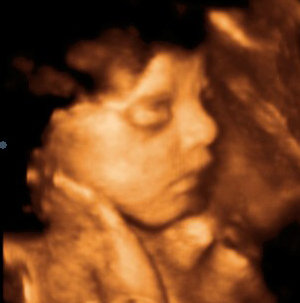

3 Д Узи Беременности ФотоВыберите Ваш пол👨 👉🏻👉🏻👉🏻МУЖЧИНА👈🏻👈🏻👈🏻👩🦱 👉🏻👉🏻👉🏻ЖЕНЩИНА👈🏻👈🏻👈🏻3 Д Узи Беременности Фото (137 фото)